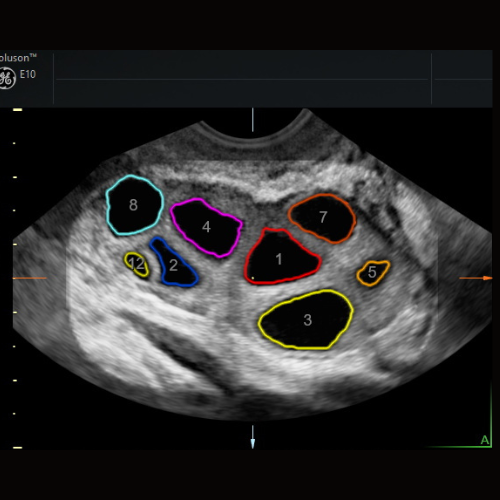

Follicular Monitoring during Fertility treatment

Follicular Monitoring at NESA Institute of Fetal Medicine Helping you understand your cycle, boost your chances, and take the stress